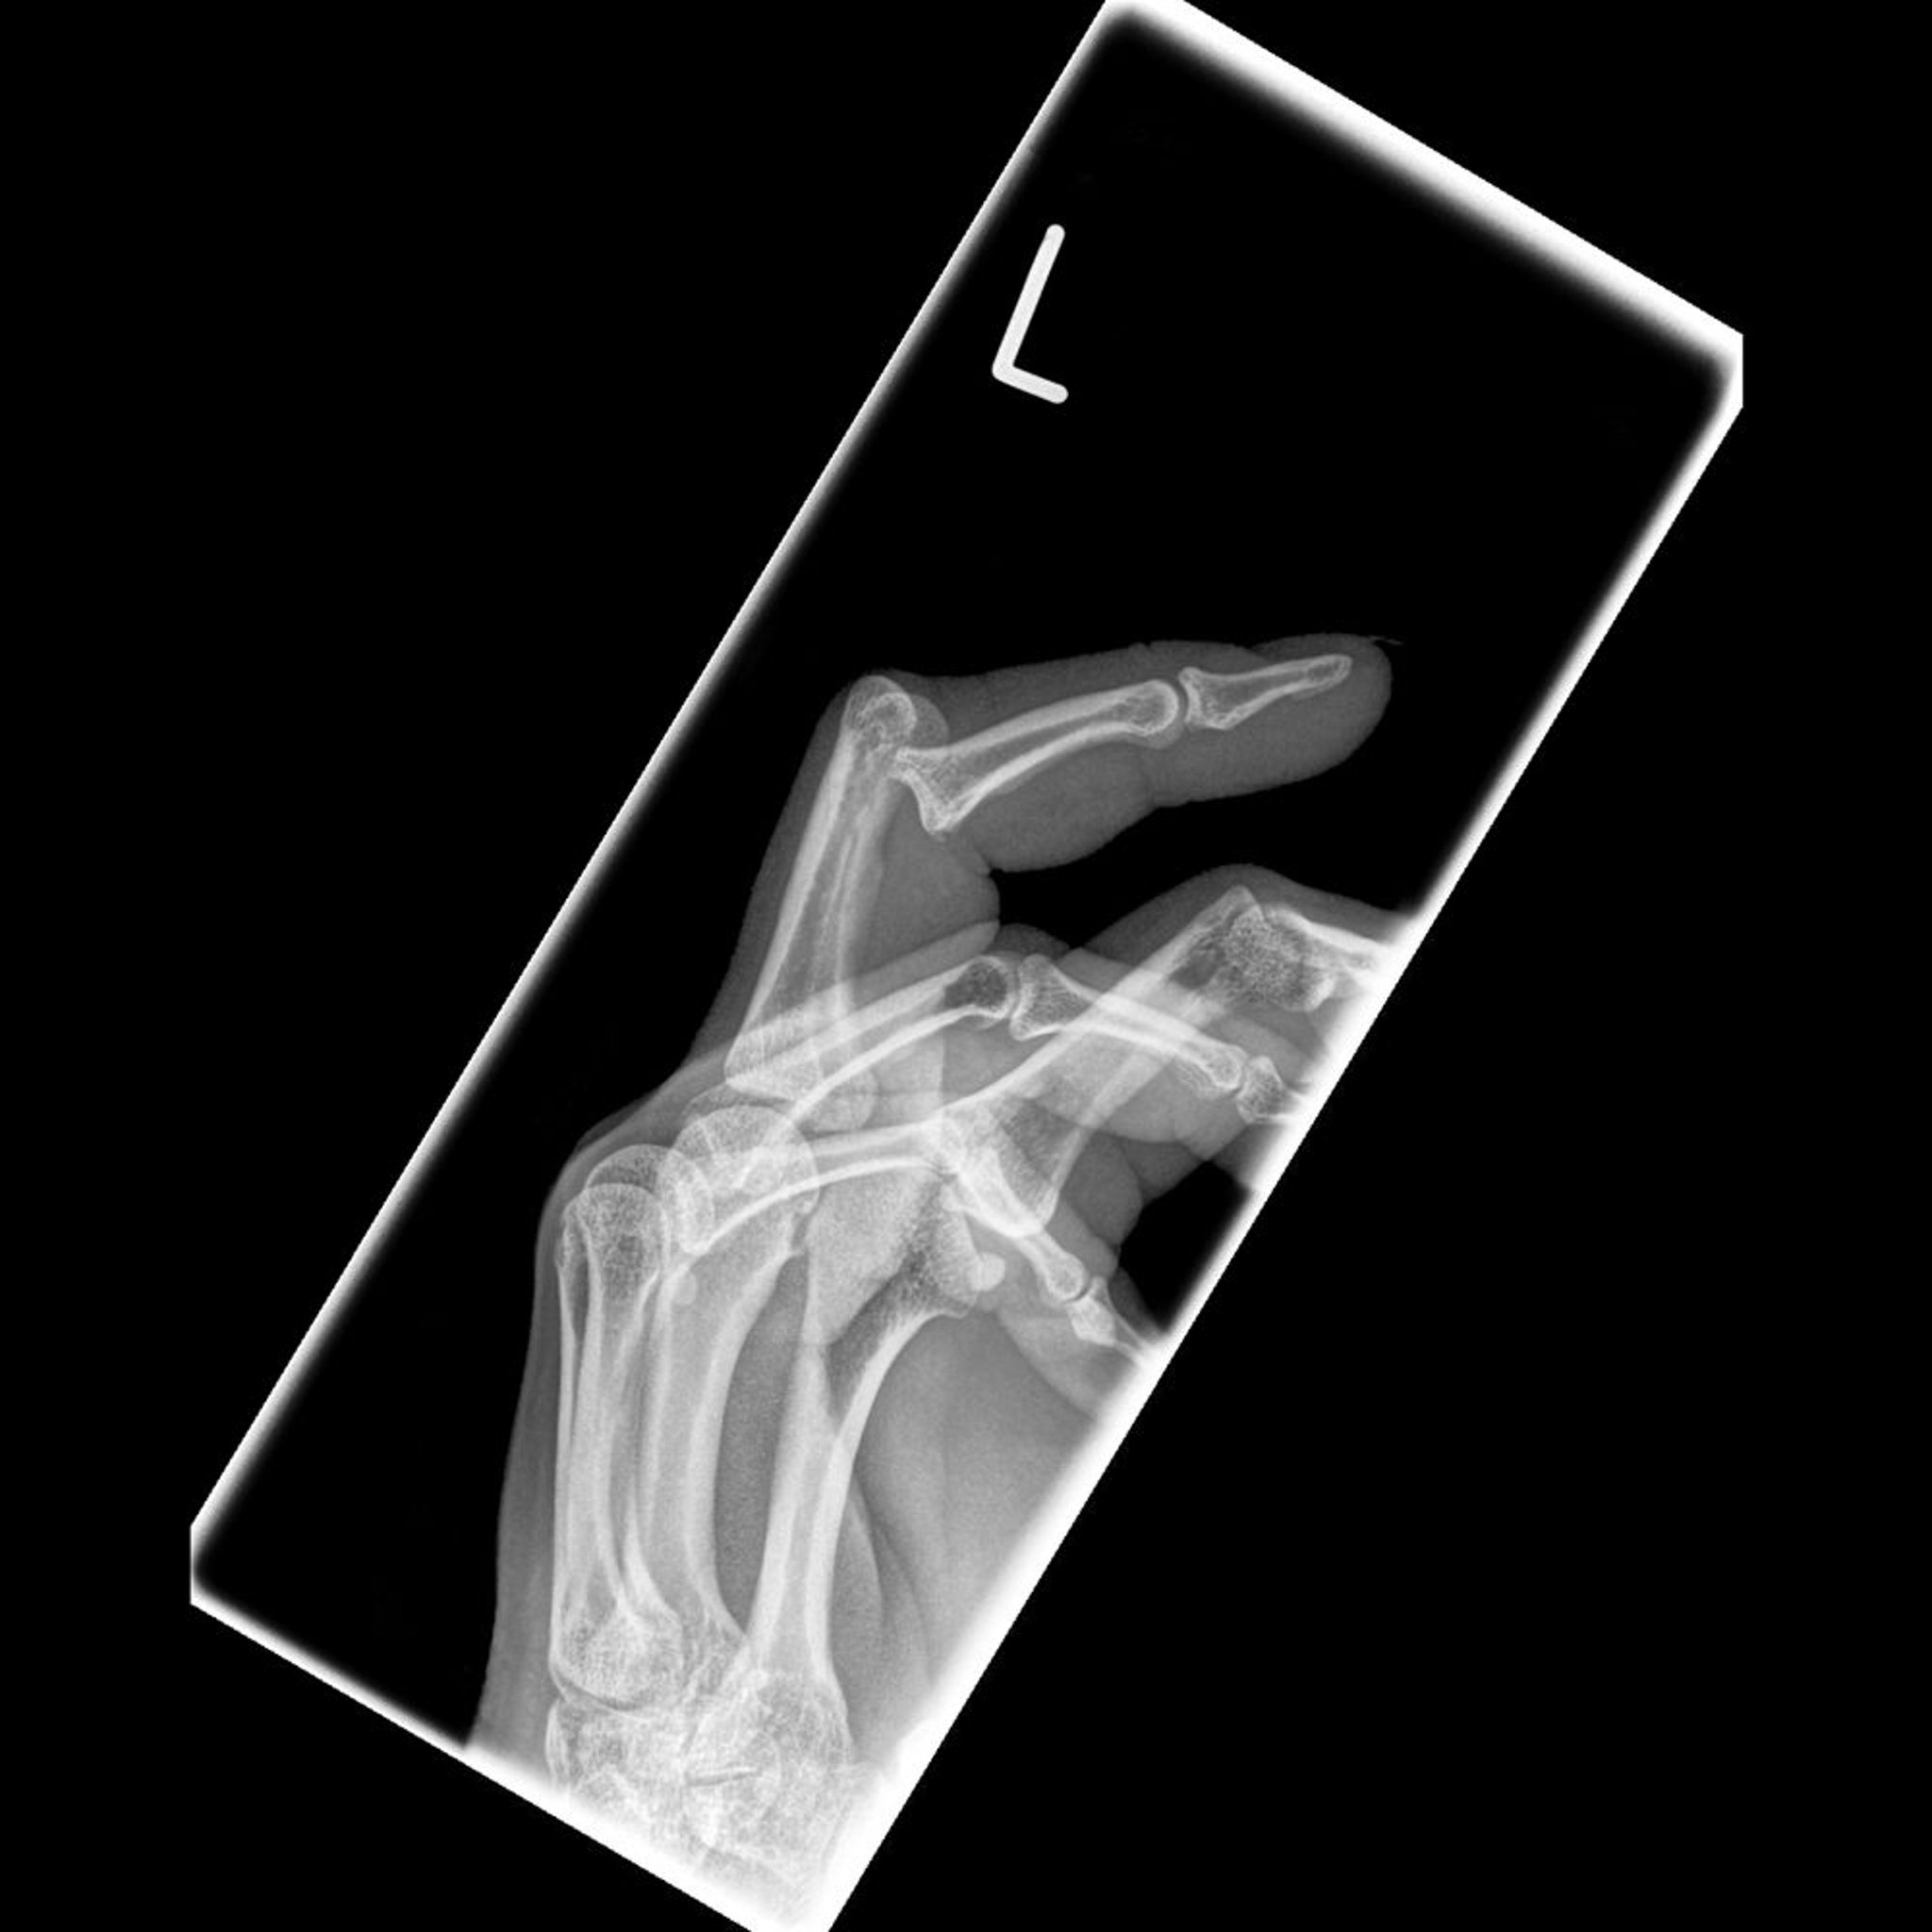

Queste foto mostrano una lussazione dorsale dell'articolazione interfalangea prossimale, accompagnata dal dito a martello.

Image courtesy of Danielle Campagne, MD.